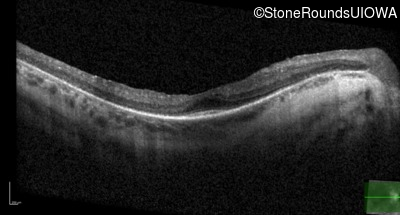

Optical Coherence Tomography - Left - 20/50 -2

Exemplar / OCT Stack